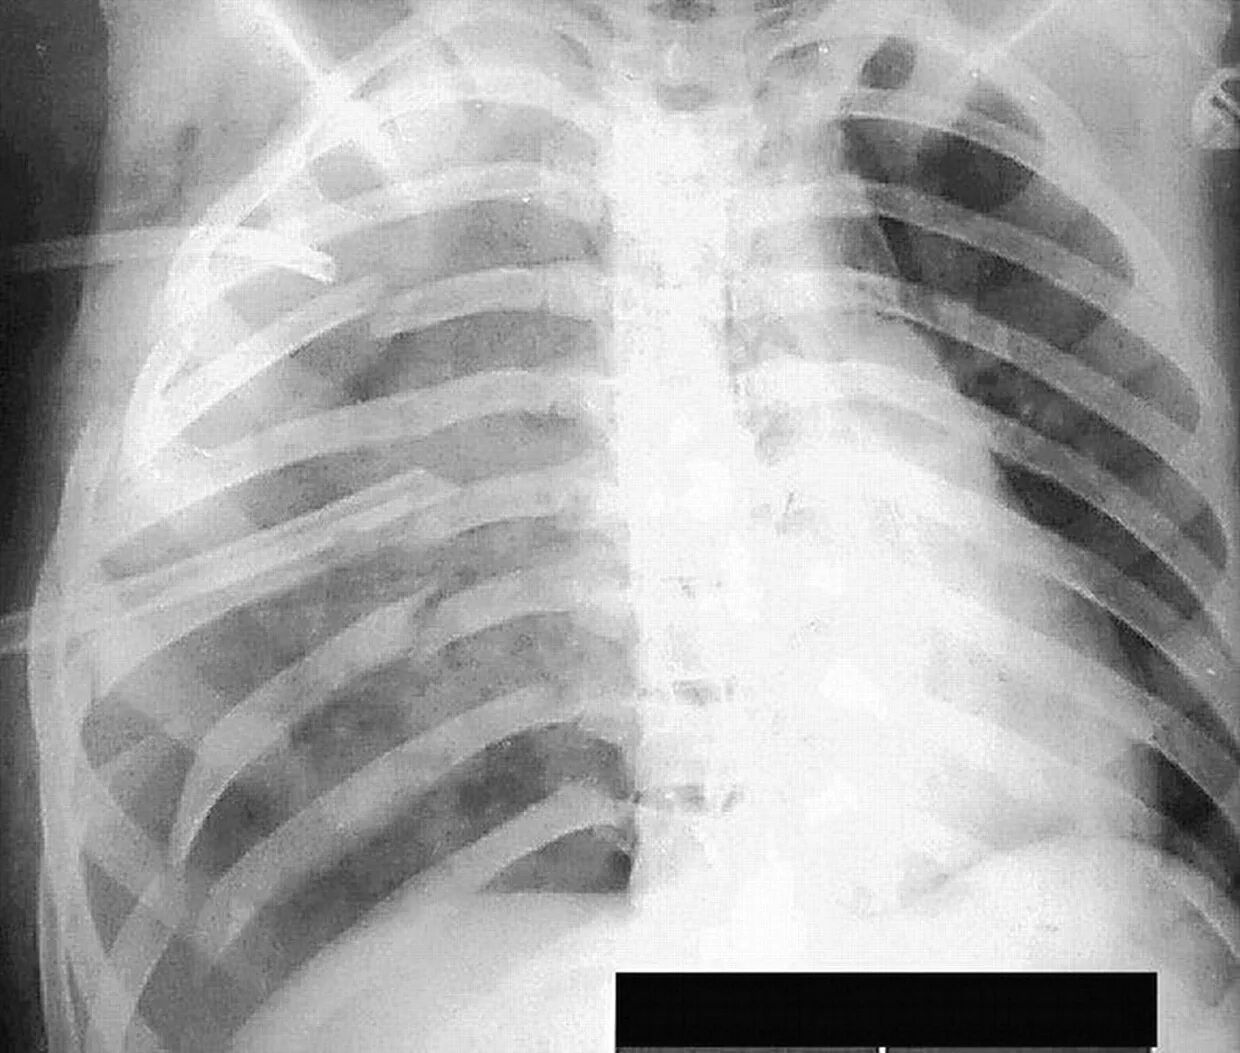

Множественные ребра